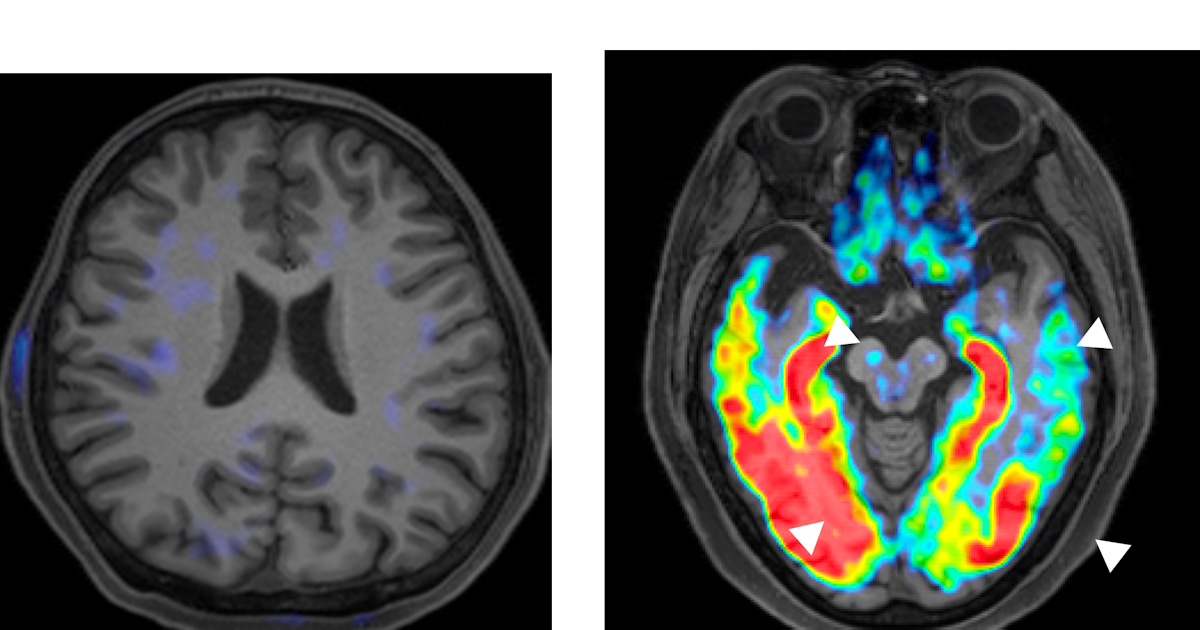

量子科学技術研究開発機構(QST)が開発した画像診断技術では、アミロイドβの蓄積を鮮明に可視化できます。

これにより、以下のような対応が可能になります。

・気分障害の背後にある認知症リスクの把握

・たんぱく質を標的とした薬による早期治療

・症状が出る前に始める「予防的な介入」への期待